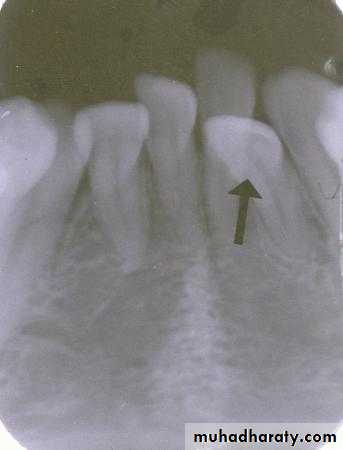

Is the composite restoration on tooth # 8 (arrows) located on the buccal or lingual?

canine filmincisor film

The restoration is located on the buccal. The tube head moves mesially from the canine film to the incisor film (x-ray beam projected more distally) and the composite moves distally, which is the opposite direction.